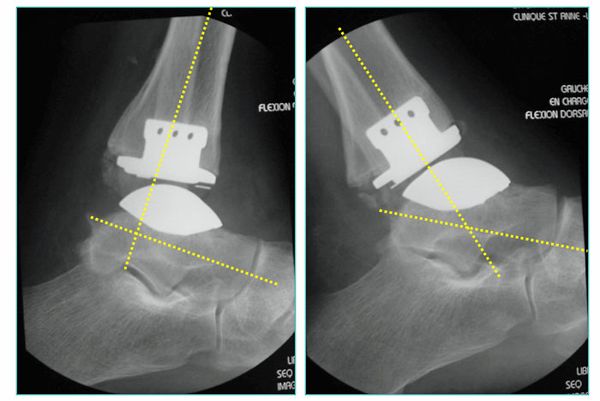

Abb.6: Zementfreie Dreikomponenten Sprunggelenkendoprothese. Bewegungsumfang nach Einbau der Endoprothese, gemessen im Röntgenbild

Das von uns verwendete Implantat ist charakterisiert als zementfreie, duale Titan-Hydroxylapatit beschichtete, nach dem mobile-bearing Prinzip konzipierte, totale Endoprothese des oberen Sprunggelenkes, bestehend aus drei Komponenten mit anatomischen Design.